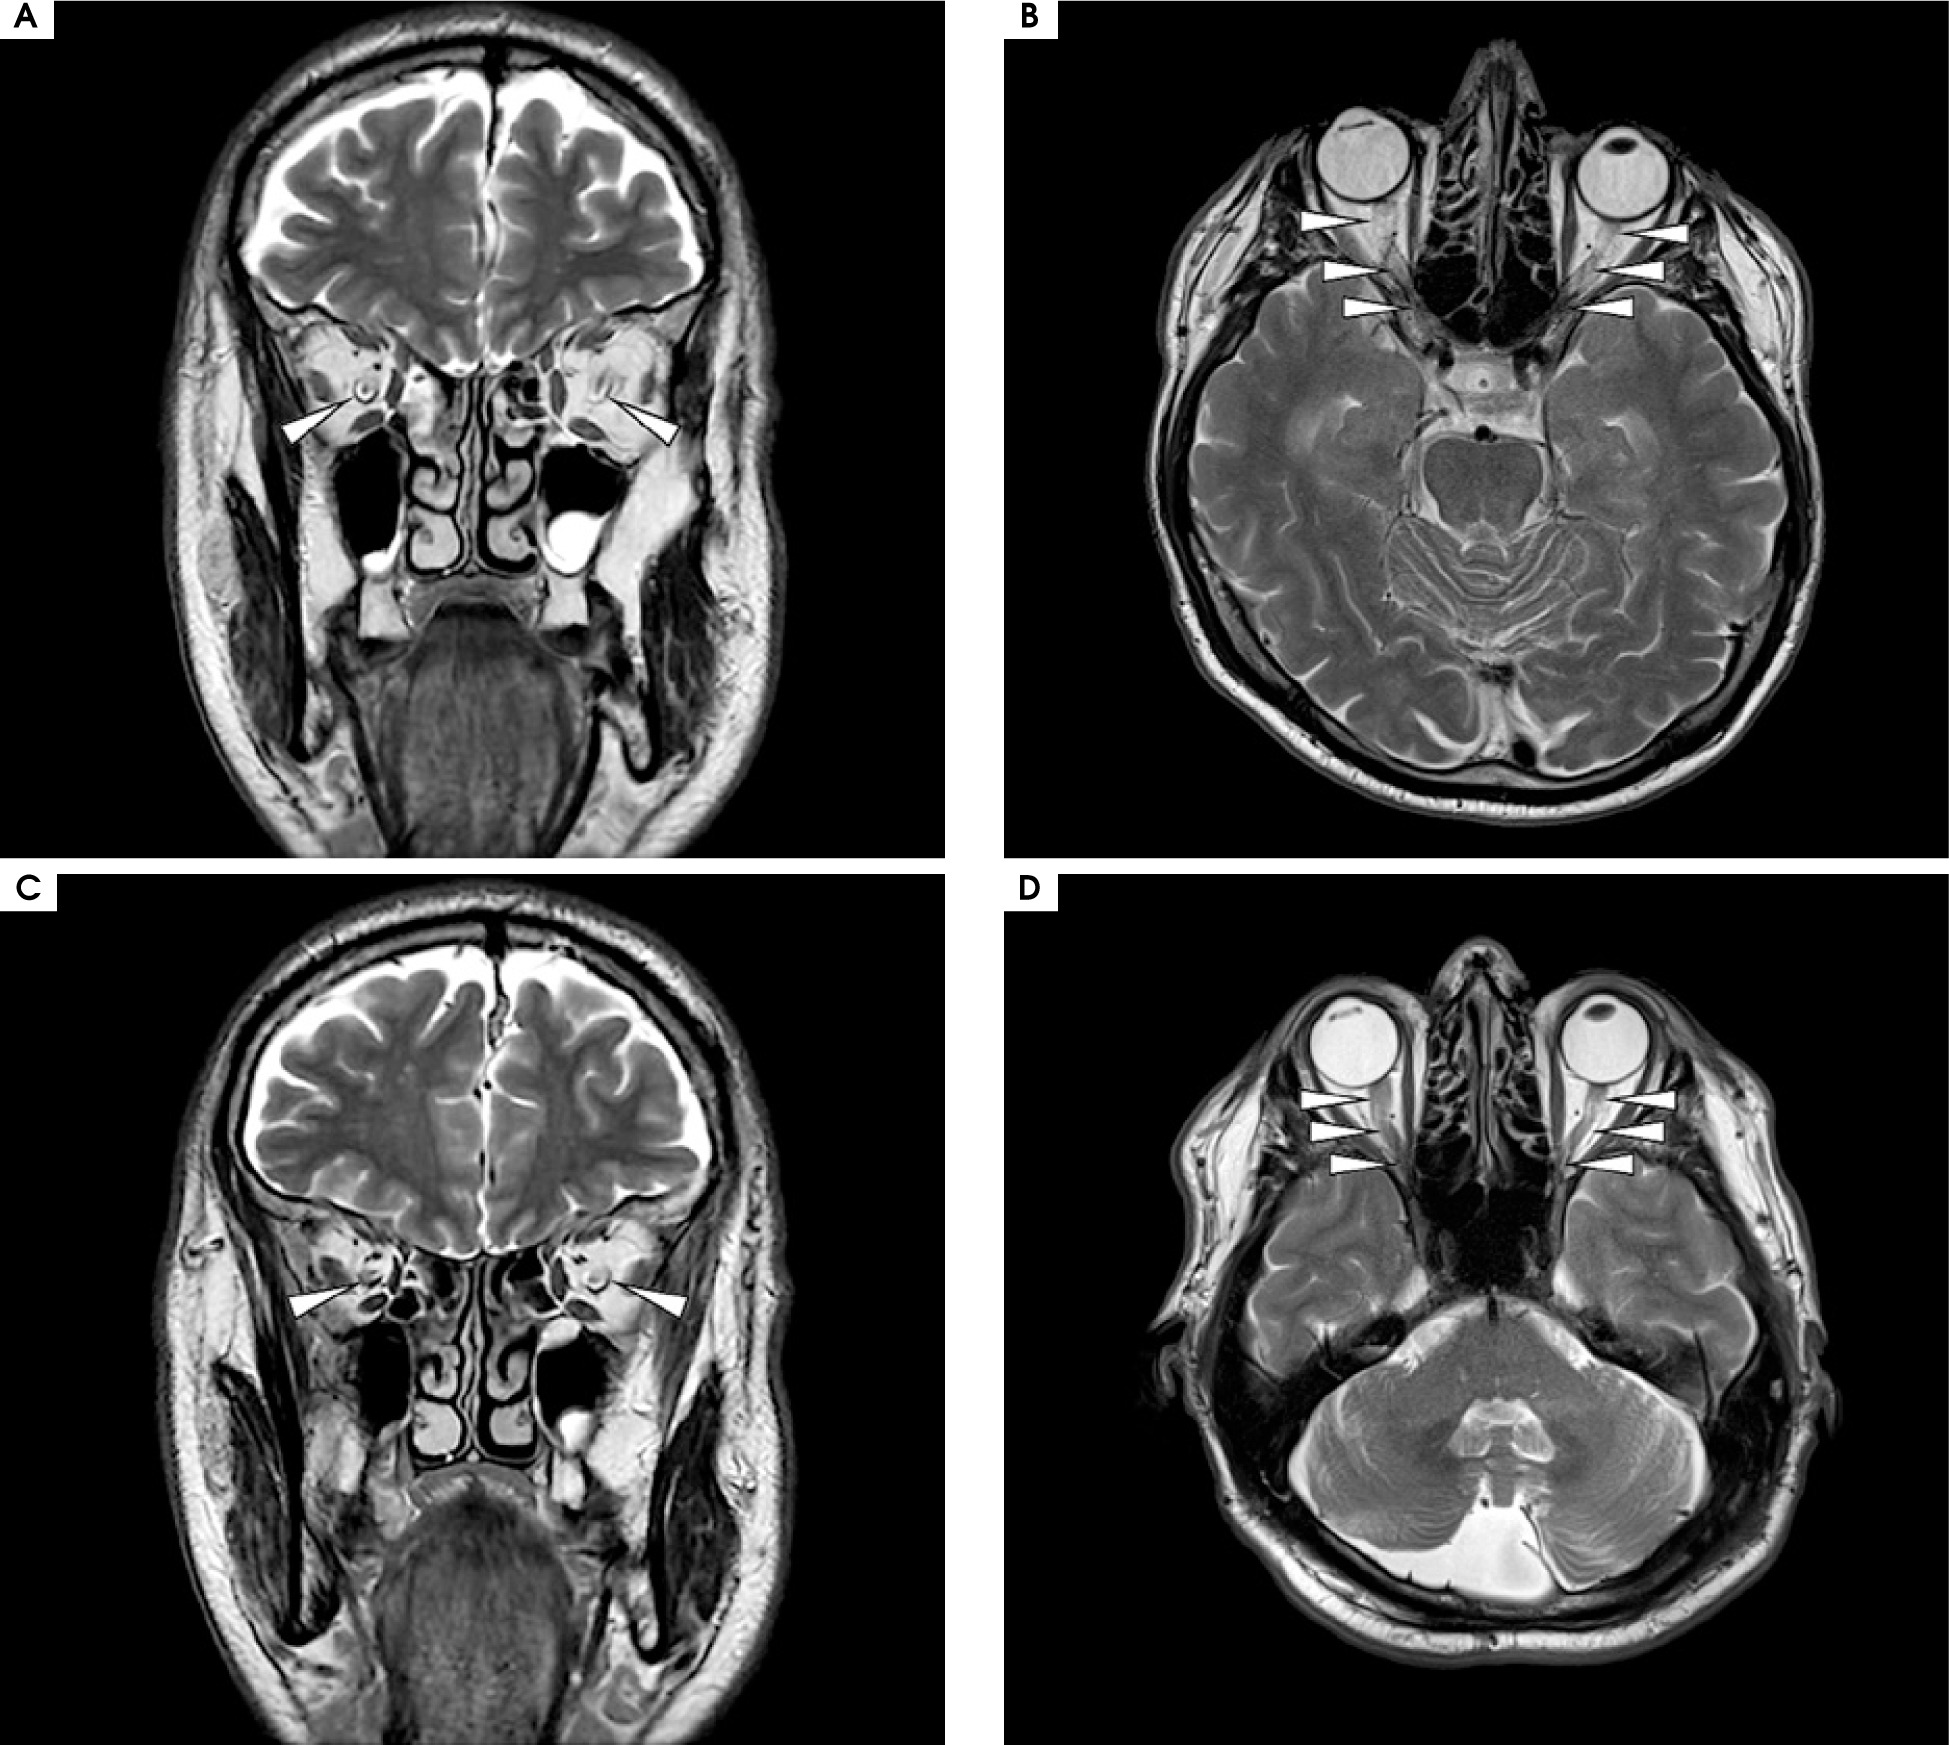

Figure II

Magnetic resonance imaging of the brain, T2 sequence. A, C) Coronal projection at different slices: bilateral optic nerve sheath enhancement is observed in the segment running through the optic nerve canal. B, D) Axial projection: bilateral longitudinal enhancement of the optic nerves in the retrobulbar segment, extending to optic chiasm and bilateral perineural sheath enhancement. No contrast enhancement was observed